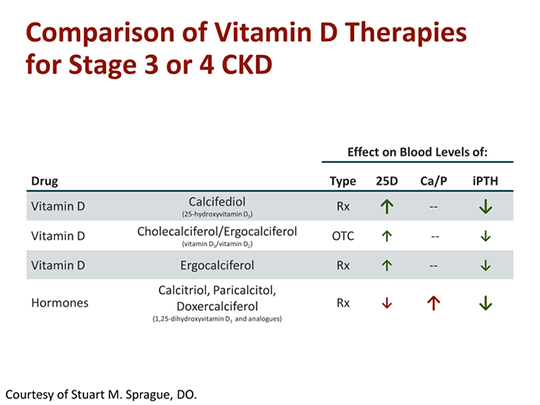

What medications are used to treat secondary hyperparathyroidism?

Drugs used to treat Secondary HyperparathyroidismDrug nameRatingView information about Sensipar Sensipar6.1Generic name: cinacalcet systemic Drug class: calcimimetics For consumers: dosage, interactions, side effects For professionals: Prescribing InformationView information about calcitriol calcitriol Off-labelRate21 more rows

There are many causes of secondary hyperparathyroidism and it can occur in any condition that causes chronic hypocalcaemia. The commonest causes are vitamin D deficiency from lack of sunlight exposure or malabsorption of vitamin D (small bowel disease, pancreatic disease, etc.), and chronic kidney disease.

A positive feedback loop leads to increased bone resorption (bone is broken down in an attempt to regulate abnormal levels of these chemicals) and hyperphosphatemia (high levels of phosphates in the blood), which causes further secondary hyperparathyroidism.

What hormones are involved in maintaining calcium and phosphorus levels?

The parathyroid glands make parathyroid hormone (PTH), which helps your body keep the right balance of calcium and phosphorous. If your parathyroid glands make too much or too little hormone, it disrupts this balance. If they secrete extra PTH, you have hyperparathyroidism, and your blood calcium rises.